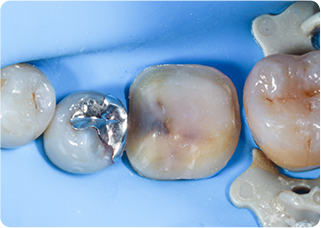

セラミックアンレー症例③

術前

ラバーダム防湿

技工物

術後

| 主訴 | 左下奥歯のむし歯の治療をしたい、良い素材での治療を希望 |

|---|---|

| 治療期間/回数 | 2週間、2回 |

| 価格(税込) | 154,000円(税込) |

| リスク・副作用 | セラミックの破損、一時的な知覚過敏が生じる場合がある |

| ポイント | むし歯を染め出すう蝕検知液を使用し、選択的にむし歯のみを除去。むし歯を除去後、すぐに詰め物でカバーをし、接着力の向上と歯を保護した。当院ではセラミック専門の歯科技工士によって精度の高いセラミックを作製。精度の高いセラミックを作製。またセラミック装着時にラバーダム防湿を行うことで、詰め物の接着効果が最大限発揮できるようにしている。 |